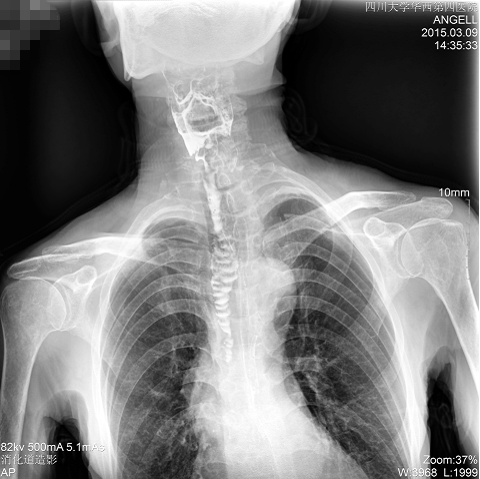

如下圖所示:該患者因吞咽時感到很難受,進(jìn)食時也經(jīng)常咳嗽故就醫(yī)診斷。華西醫(yī)院醫(yī)生使用動態(tài)DR為病人進(jìn)行消化道造影診斷,要求他吞鋇后發(fā)現(xiàn),食道各段通過順利,形態(tài)規(guī)則,雙側(cè)梨狀窩不對稱左側(cè)稍淺,多次吞咽動作后,仍見鋇劑滯留,并見鋇劑進(jìn)入氣管,屬于會厭征陽性。會厭功能紊亂,鋇劑進(jìn)入了氣管。

圖為正位:通過動態(tài)影像可以清楚看到鋇劑進(jìn)入了支氣管道且雙側(cè)梨狀窩不對稱